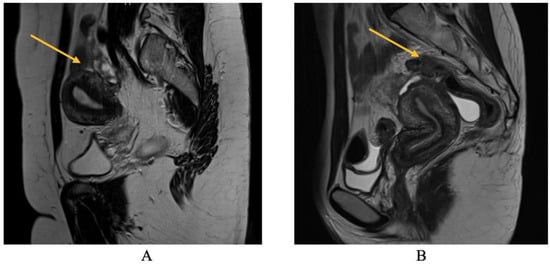

As will be elaborated upon in the forthcoming discussion section, the identification of parametrial lesions may prove more challenging in the absence of collaboration with a radiologist possessing specialized expertise in recognizing DIE lesions. The parametrial nodule manifests as a hypointense thickening or evidence of a mass with irregular contours situated in the posterior uterine region, as depicted in Figure 4 [16].

In relation to parametrial lesions, the sensitivity of TVS and MRI was found to be 9% and 27.14%, respectively. The diagnostic accuracy of TVS and MRI exhibited similar levels of specificity. Specifically, TVS had a specificity of 97%, while MRI exhibited a specificity of 89.19%. Among a total of 256 patients, a significant majority of 189 individuals had parametrial lesions associated with intraoperative endometriosis. Consequently, the surgical intervention of laparoscopic excision was employed to address and remove these lesions. Among the observed cases, 31.21% exhibited left DIE parametrial lesions, while 20.63% displayed right DIE parametrial lesions. Additionally, 48.14% of the cases presented with bilateral lesions, as illustrated in Figure 4.

The precision of the two techniques was found to be 32% for TVS and 40.11% for MRI. The ultrasound diagnosis is not consistent with the intraoperative diagnosis for parametrial lesions of endometriosis, the association not being statistically significant according to the exact statistical tests Chi-square test and Fisher’s exact test (p = 0.172).

The MRI is consistent with the intraoperative diagnosis for parametrial lesions of endometriosis, the association being statistically significant according to the exact statistical tests Chi-square test and Fisher’s exact test (p = 0.049).

Figure 4. MRI aspect on T2 sagittal: parametrial endometriosis nodule.